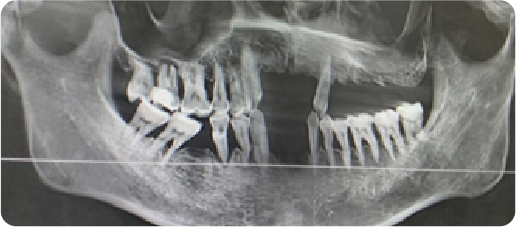

Multiple Dental Implants Case

BEFORE

VS

AFTER

Name:Mr QinAge:34

Evaluation: Missing two or three maxillary anterior teeth.

Treatment Plan:Three implants were placed to anchor a bridge that replaces five teeth,with two artificial teeth suspended in between.

Patient Feedback:Experience a secure, long-lasting solution that protects your healthy teeth,feels comfortable, and looks bcautifully natural.

For Prevention:Consistent care, including diligent oral hygiene and regular professional maintenance,is essential for the long-term durability of dental implants.